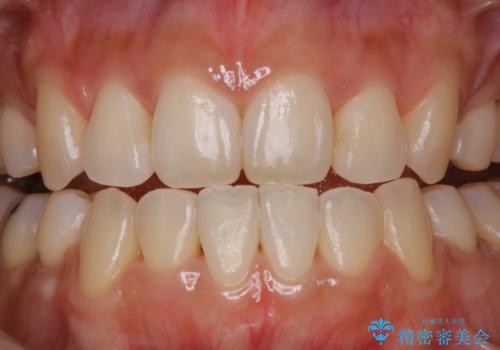

- 約1年前に矯正治療が終了し、その後のメンテナンスを行っている方です。矯正のチェックもかねてクリーニングも希望とのことでした。

PMTC(自費クリーニング)30分コースを行いました。

定期的なメンテナンスをして頂いていること、ご自身でのケアをかなり丁寧にされていていることで、歯石や着色の量がさほど多くなかったため30コースで全体的なクリーニングが可能でした。